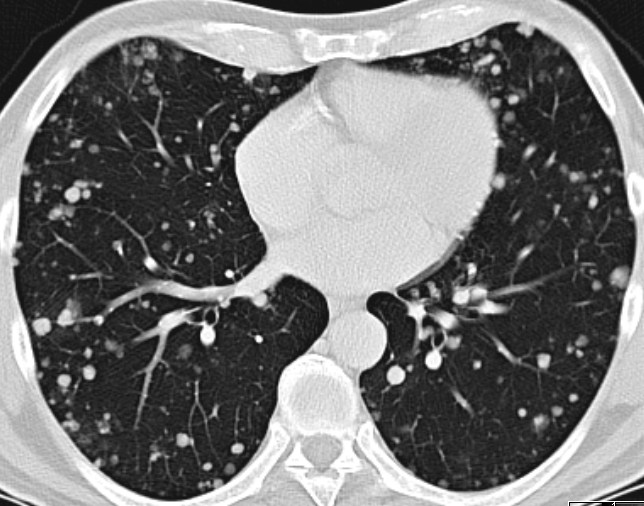

Lungenmetastasen.![]() |